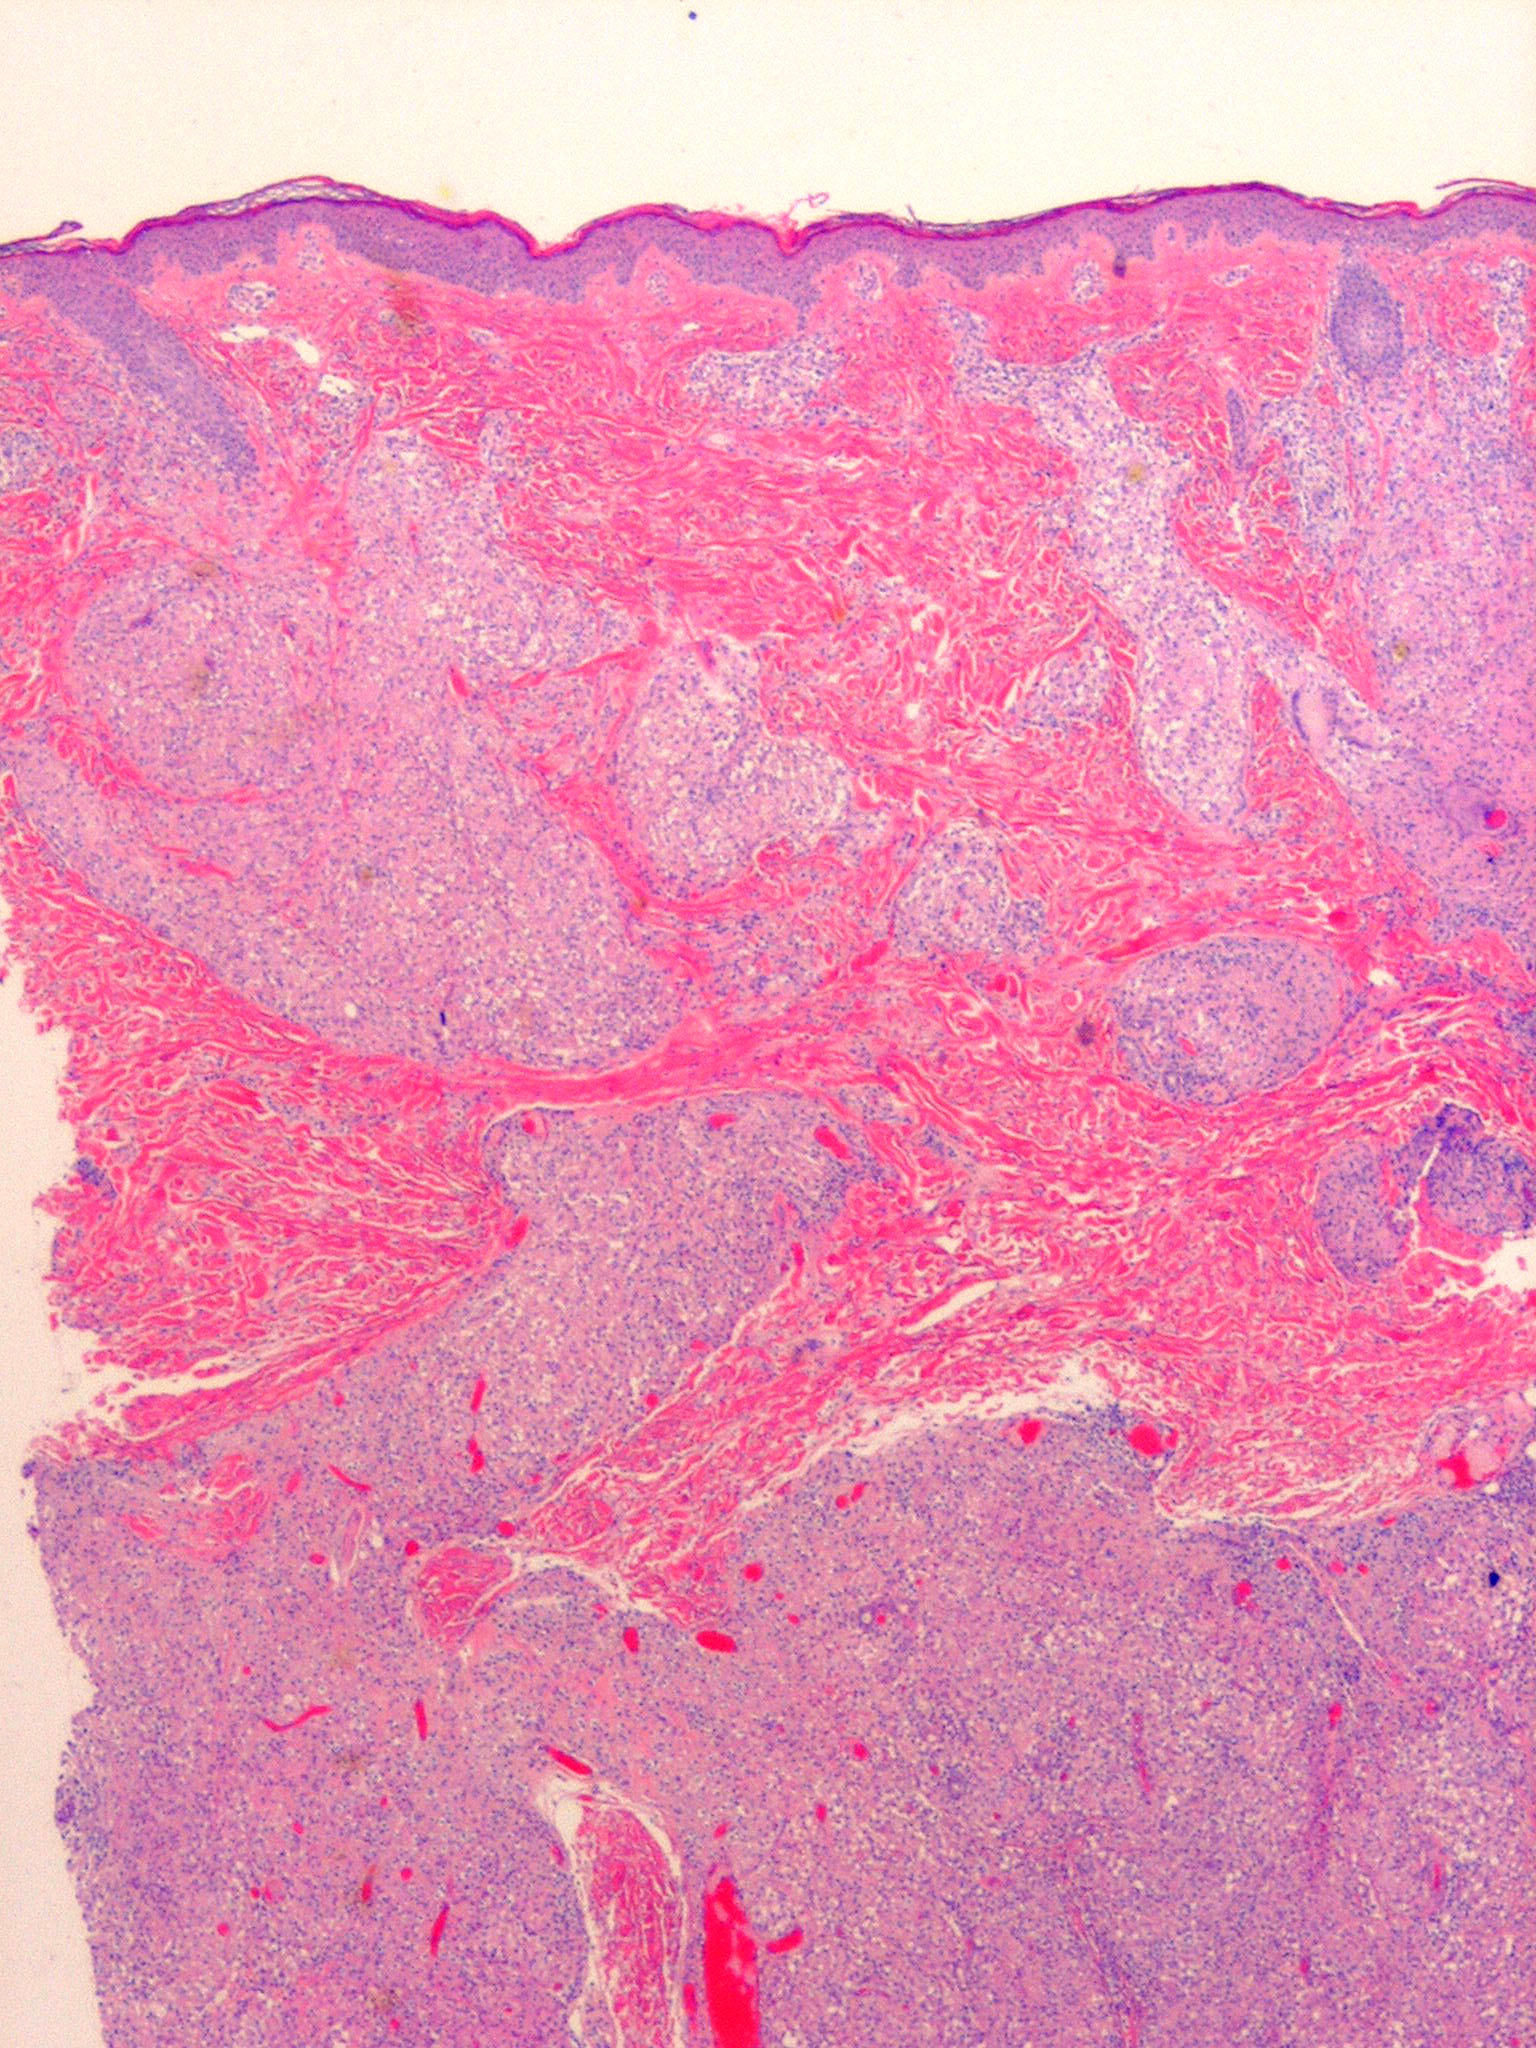

Like lesions in other organs, the cutaneous lesions of chronic, persistent sarcoidosis are characterized by the presence of circumscribed collections of epithelioid histiocytes-so-called epithelioid cell tubercles-which show little or no necrosis .

The papules, plaques, and lupus pernio-type lesions show variously sized aggregates of epithelioid cells scattered irregularly through the dermis with occasional extension into the subcutis (. In the erythrodermic form, the infiltrate shows small granulomas in the upper dermis intermingled with numerous lymphocytes

and, rarely, also giant cells . Typical sarcoidal granulomas are found in the ichthyosiform lesions , in ulcerated areas , and in atrophic lesions . Verrucous sarcoid exhibits prominent associated acanthosis and hyperkeratosis . Biopsies of

hypopigmented sarcoid may reveal granulomas, which may have a perineural component or fail to reveal granulomas . In subcutaneous nodules, larger epithelioid cell tubercles lie in the subcutaneous fat .